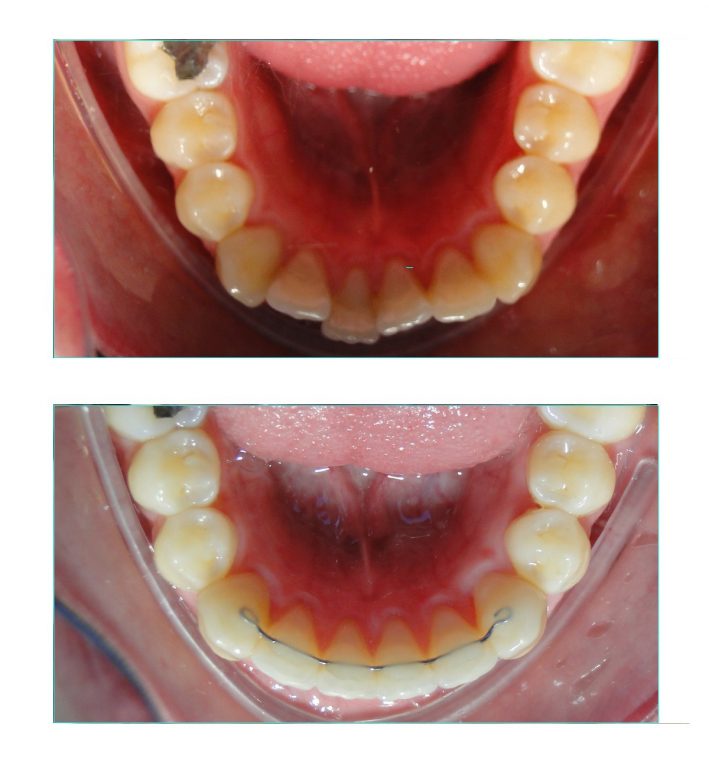

Foi preciso fazer a expansão das arcadas e também o nivelamento e alinhamento dos dentes.

A expansão foi obtida apenas com o uso do aparelho fixo. Não foi usado um disjuntor palatino ou qualquer outro tipo de dispositivo expansor.

Na arcada inferior vemos uma contenção ortodôntica fixa reta. Na arcada superior foi usada uma contenção removível de acetato associada à uma contenção fixa, que foi instalada posteriormente.